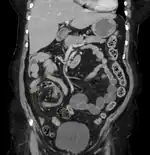

CT scan of a small bowel volvulus. It shows two juxtaposed segments of narrowing, which is the spot of mesentery rotation. The other signs indicate strangulation.- An x-ray of a person with a small bowel volvulus.

CT scan of a cecal volvulus